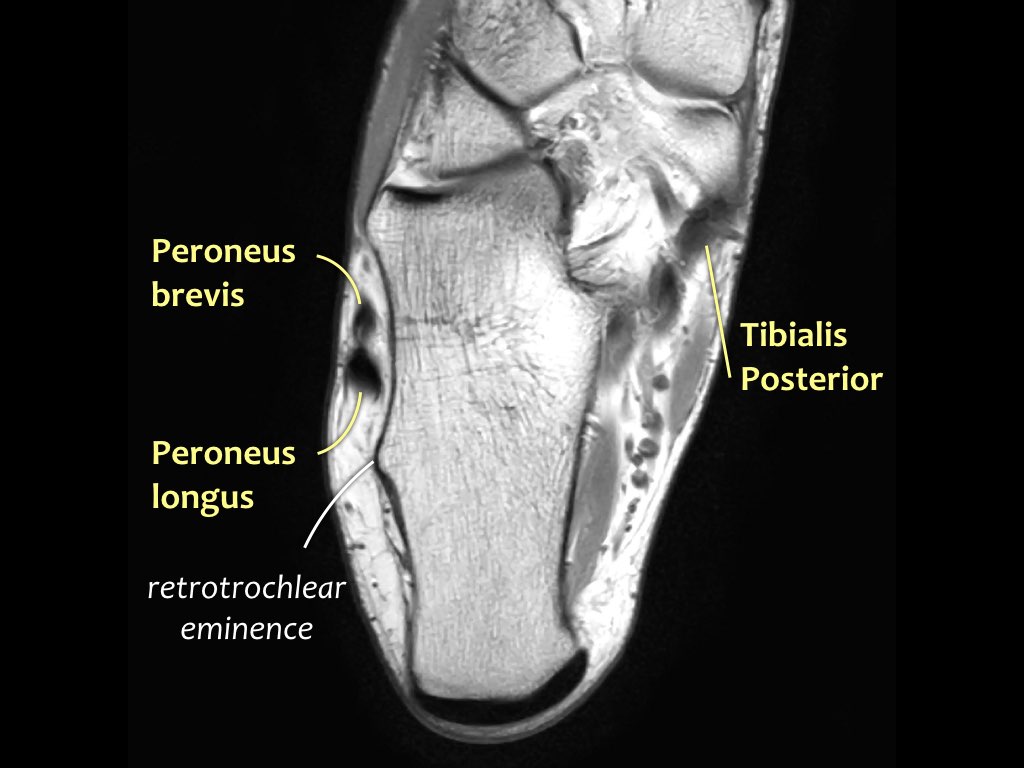

- Khoang ngoài

- Gân cơ mác dài (Peroneus Longus)

- Gân cơ mác ngắn (Peroneus Brevis)

Gân cơ chày sau

Gân cơ chày sau là gân bị tổn thương thường gặp nhất.

Bệnh lý gân biểu hiện bằng tình trạng sưng to bất thường của gân, tuy nhiên cần lưu ý rằng gân chày sau bình thường có thể có kích thước gấp đôi gân cơ gấp các ngón chân dài.

Rối loạn chức năng gân chày sau thường gặp hơn ở phụ nữ và những người trên 40 tuổi.

Tình trạng này gây ra đau và sưng ở mặt trong cổ chân, cùng với biến dạng bàn chân bẹt mắc phải.